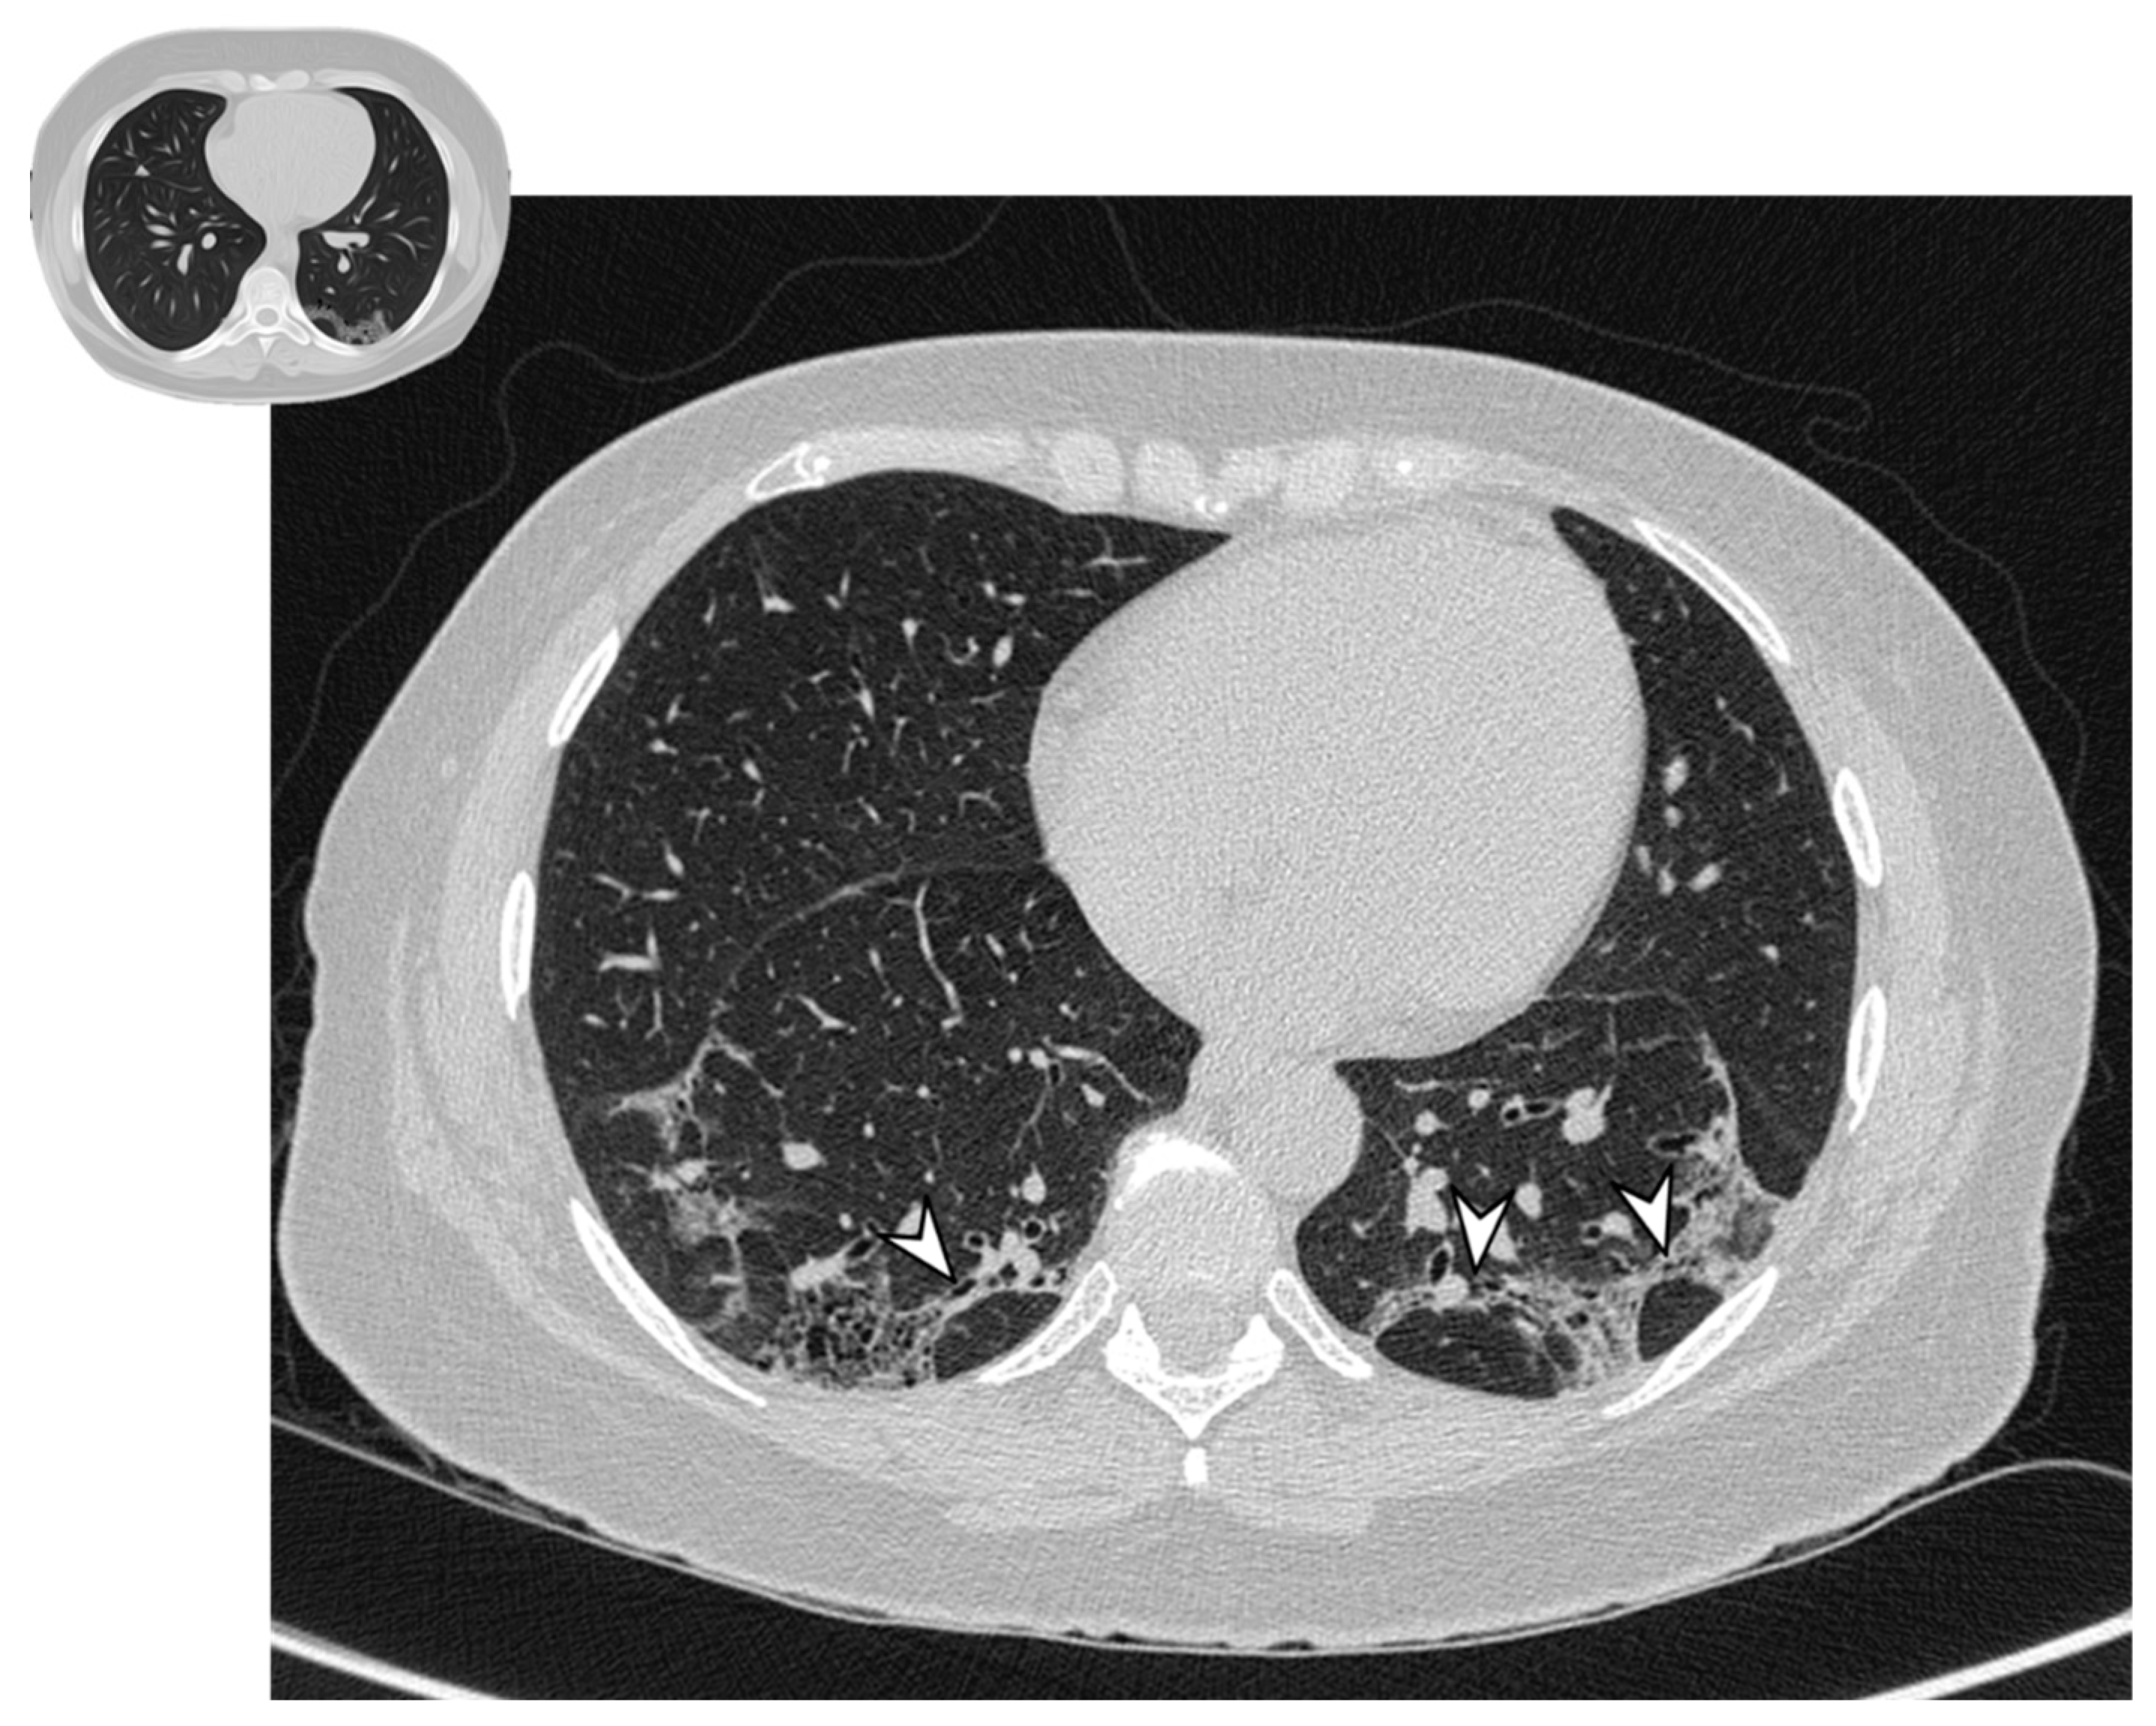

Figure 2. Typical pattern: multifocal and asymmetrical parenchymal consolidations (arrowheads), with peripheral distribution. These lesions may reproduce an air bronchogram sign in the context.

The classical form of COP is characterized by multifocal parenchymal consolidations, often bilateral and asymmetrical. These findings are usually described as patchy or with peripherical or peribronchial predominance in lower lobes. They tend to migrate, disappearing spontaneously and appearing in different sites (Figure 2) [22,26]. Consolidations may be associated with GGOs; usually, these lesions may reproduce an air bronchogram sign in the context [22]. At the moment of the onset, this typical pattern has been encountered in about 75% of patients [22,24,25,26].